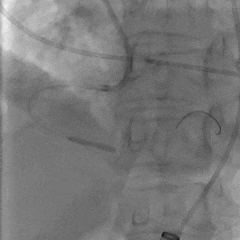

瓣膜初始定位

第一次释放,瓣膜位置偏高,选择回收

第二次瓣膜释放

造影评估,瓣膜位置可

右侧位造影,瓣膜深度可

多角度评估,瓣膜位置可,少量瓣周漏

脱钩后造影,瓣膜无位移,可见瓣周漏

20mm球囊后扩,瓣膜形态改善

后扩后评估,可见少量瓣周漏

最终瓣膜位置稳定